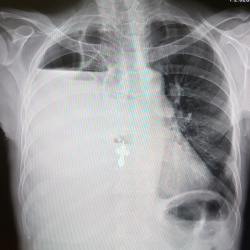

Добрый день. Рентгенограмма профилактическая. Возраст пациента 39 лет, жалоб не предъявляет. Первый снимок - сегодняшний, второй - от 2017 г. Не понравился левый лёгочный корень, но с учётом архива...